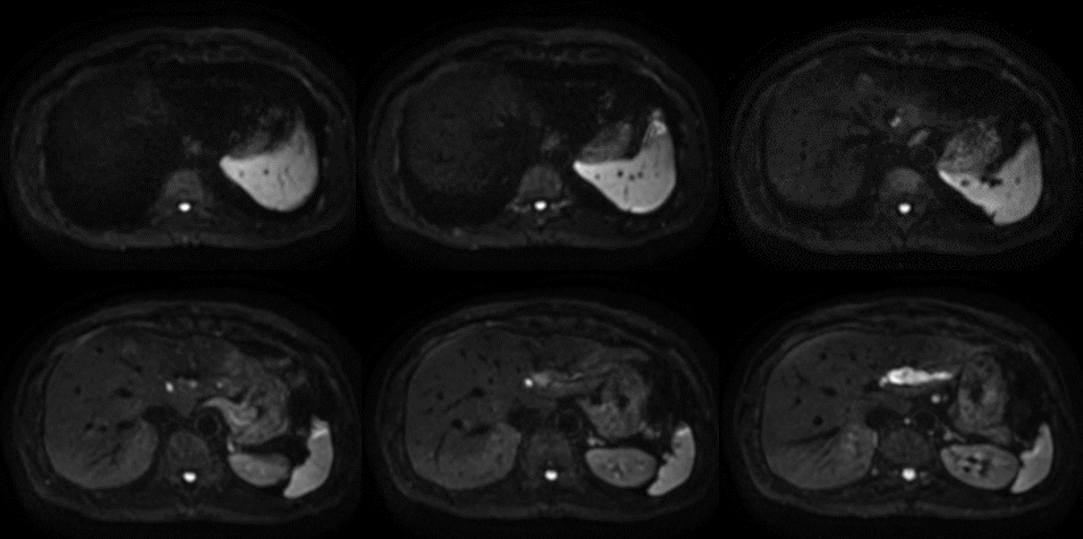

MR29新機能を用いた臨床例。図表8に膵体部がん症例を供覧する。膵体部にDWI高信号を示し主膵管の拡張を来している。

DWI Enhancement

今回のバージョンアップでは、上腹部におけるDWIのシェーディングが抑制される拡張機能が追加されている。DWIはもともとMPGにより動きの有無をコントラストとした画像であるため、動きに対して非常にセンシティブな撮像法である。上腹部領域は、心拍伝播などのわずかな動き(non-diffusive motion)の影響を受けやすい部位である。それにより同領域では位相分散による信号低下を引き起こす原因となっている。今回のDWI Enhancementは、わずかな動き(non-diffusive motion)による位相分散に対して信号低下が起こりにくいように、DWIのリコンアルゴリズムを最適化した新しい画像再構成技術が搭載されている。

今回の拡張機能によりDWIの安定した画像が取得でき、信頼性の高い画像が確実な診断へと導いてくれている。